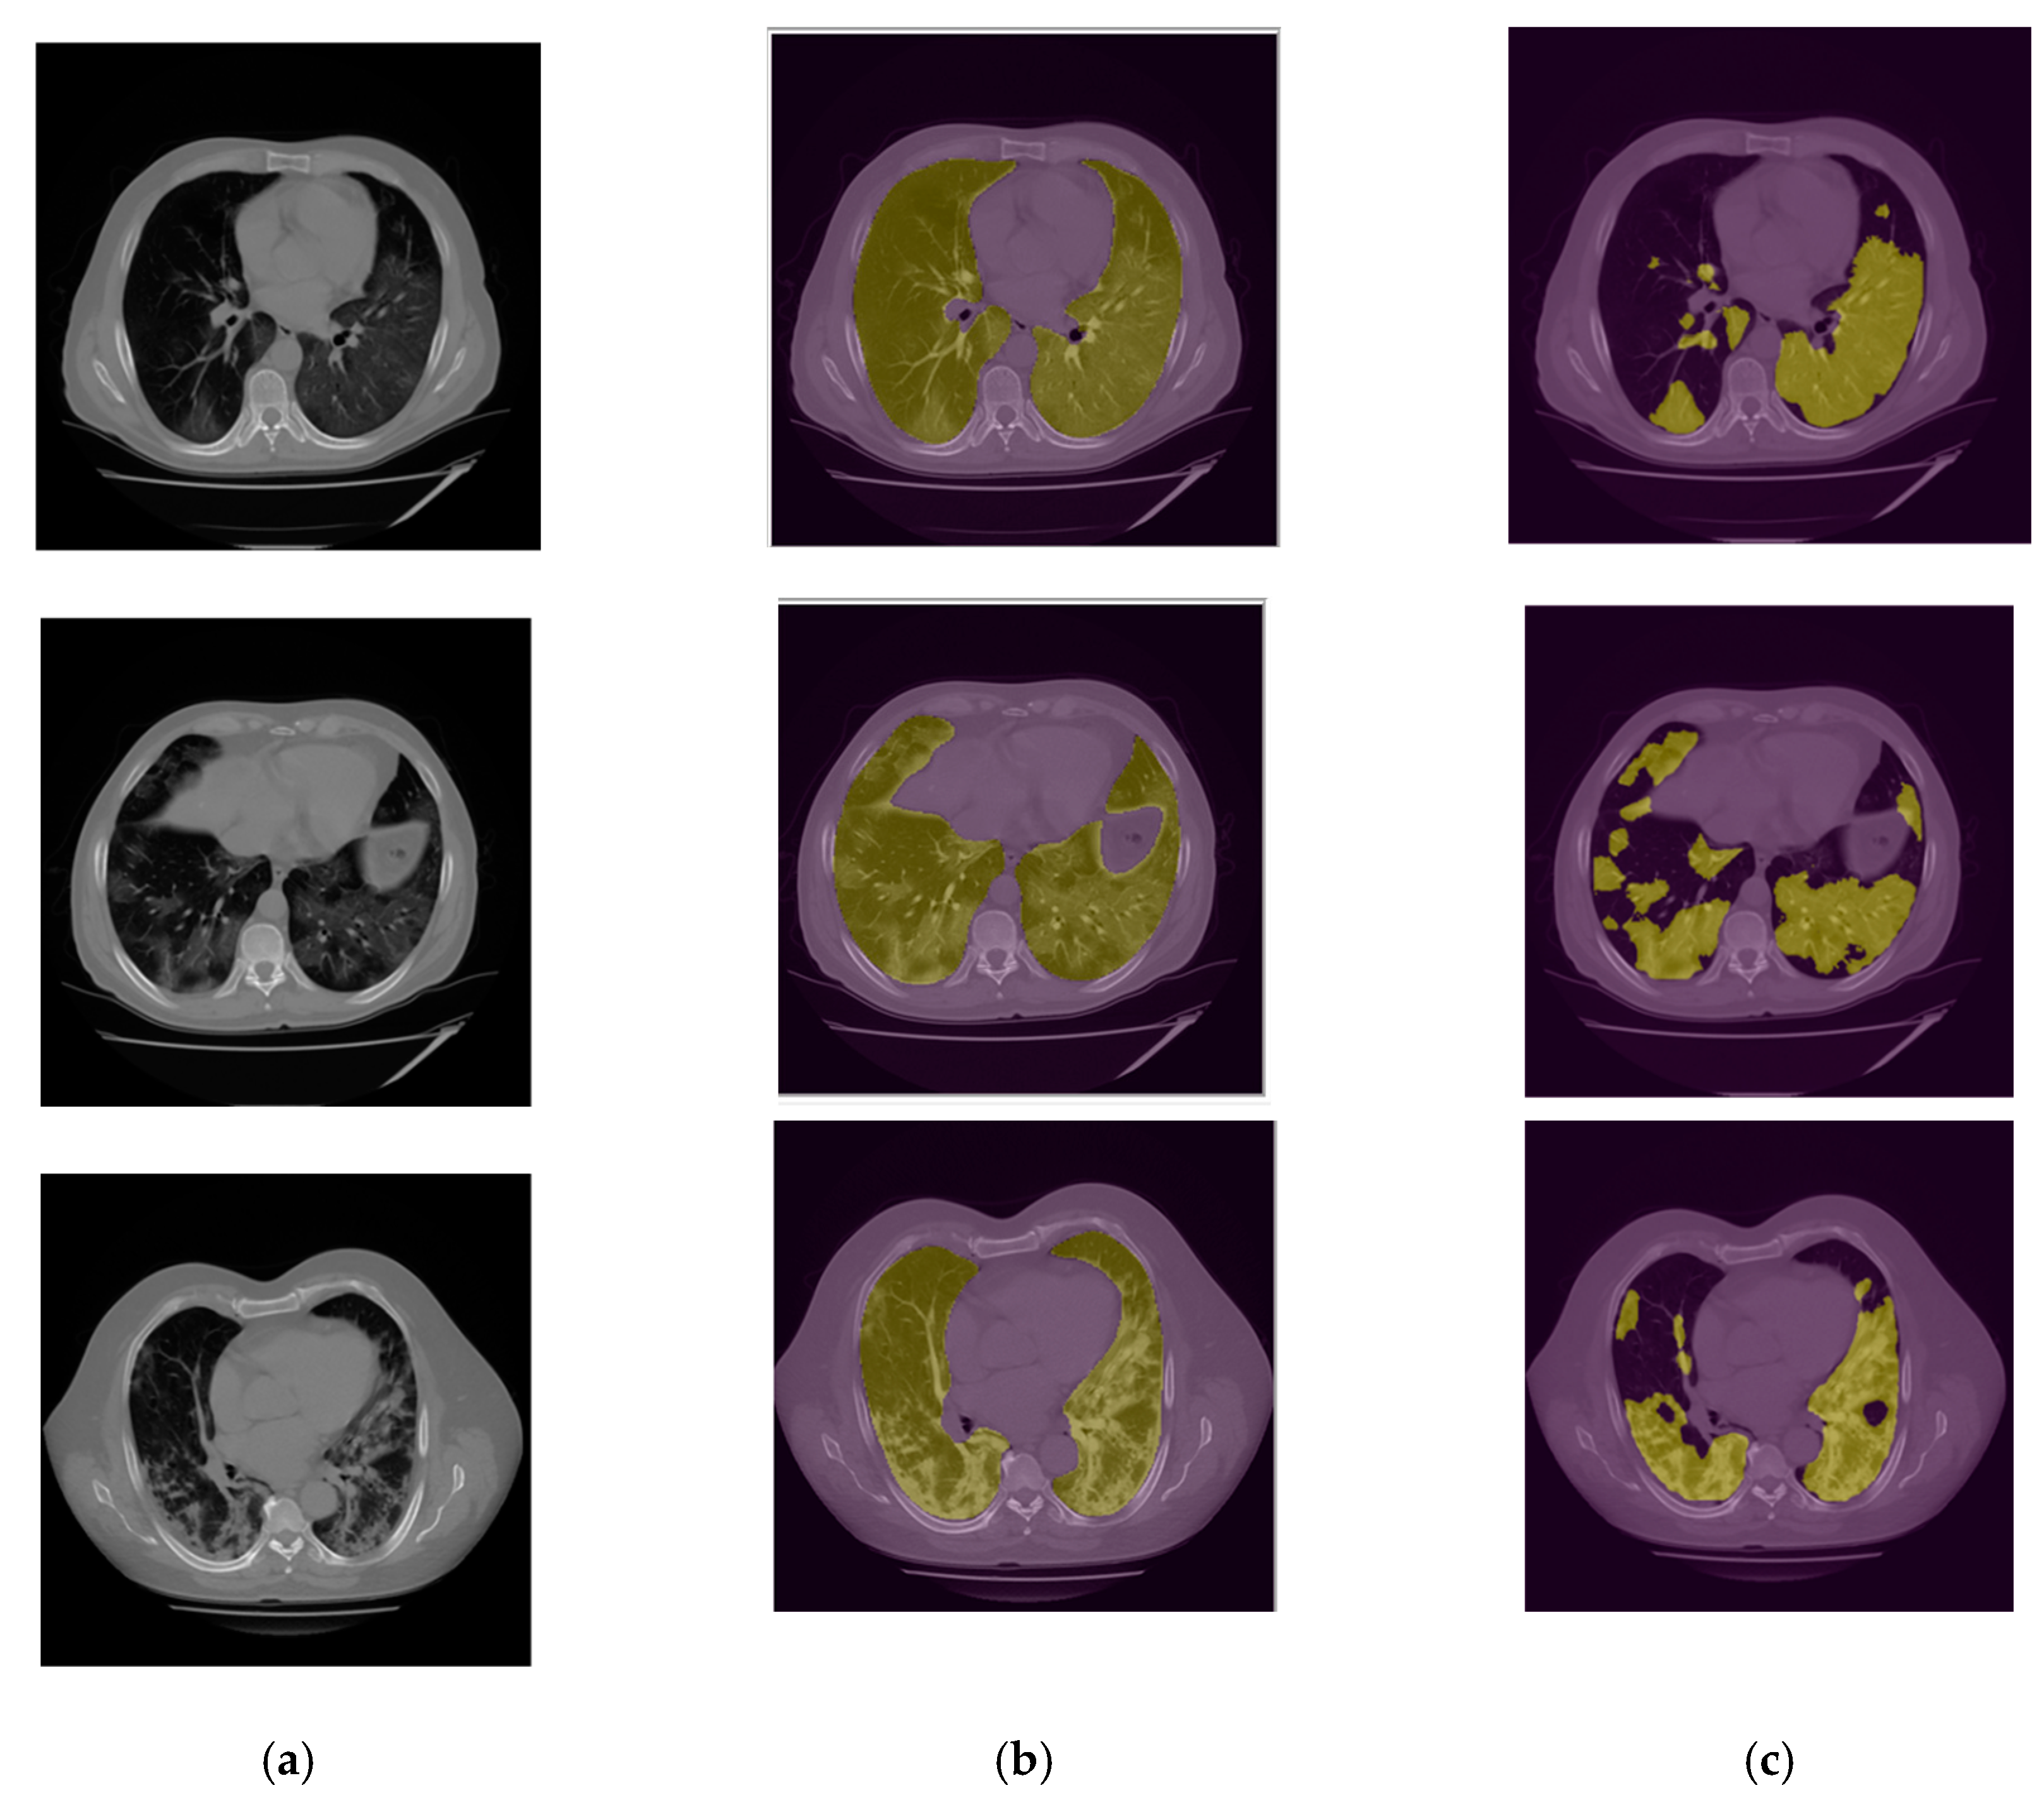

2.3.1. Lung Segmentation

2.3.2. Infection Area Segmentation

2.3.3. Segmentation of GGO and Consolidation Patches